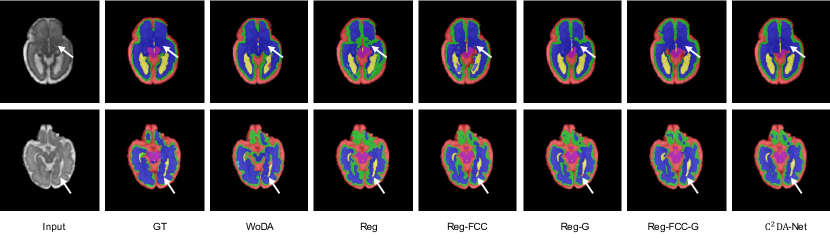

Refer to caption

Figure 5: Qualitative comparison of different methods for subjects at 22 GWs, 25 GWs, 27 GWs, 30 GWs, and 33 GWs, respectively. Typical results are shown row-by-row. The red, green, deep blue, yellow, shallow blue and purple stand for CSF, GM, WM, ventricles, cerebellum, and brainstem, respectively.

Next, we compare our method with state-of-the-art UDA methods to validate its effectiveness. The quantitative and qualitative comparisons are presented in Table 1, Fig. 5 and Fig. 6. Our method achieves the best performance in the segmentation of six tissues and multi-view images, demonstrating the advantages of the proposed method in domain adaptation based segmentation. An interesting observation is that the three state-of-the-art UDA methods provide relatively small performance improvement, which can be explained from two aspects. First, the limited intensity contrast among different tissues can pose a challenge for methods that align different domains in image space, which can result in limited improvement in low-intensity contrast areas. Second, the target and source domain data are with the same imaging modality (i.e., T2-weighted MR images), making it difficult to extract domain-invariant features and avoid falling into a local optimum during adaptation. The low Dice accuracy of ANTs suggests that the registration process is not precise enough for achieving accurate segmentation. To demonstrate the advantage of our method, we provide five qualitative segmentation samples from different GWs in Fig. 5. It can be observed that our method matches the ground truth well, especially at the boundaries between brain tissues with limited intensity contrast.